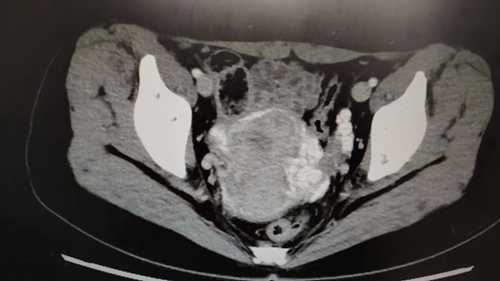

憑借著豐富的臨床診療經(jīng)驗(yàn),張濤教授敏銳地懷疑小雪患上了盆腔淤血綜合征,隨后的下腹部盆腔的CT平掃增強(qiáng)檢查更是直接“實(shí)錘”了這一判斷。

手術(shù)過程中,靜脈造影就像給血管來了一場 “高清直播”,清晰地展示出左側(cè)卵巢靜脈明顯迂曲增粗,造影劑滯留延遲,盆腔靜脈叢血流瘀滯,左側(cè)卵巢靜脈叢多處病灶更是呈現(xiàn)出團(tuán)狀迂曲增粗、側(cè)枝豐富的“亂象”。